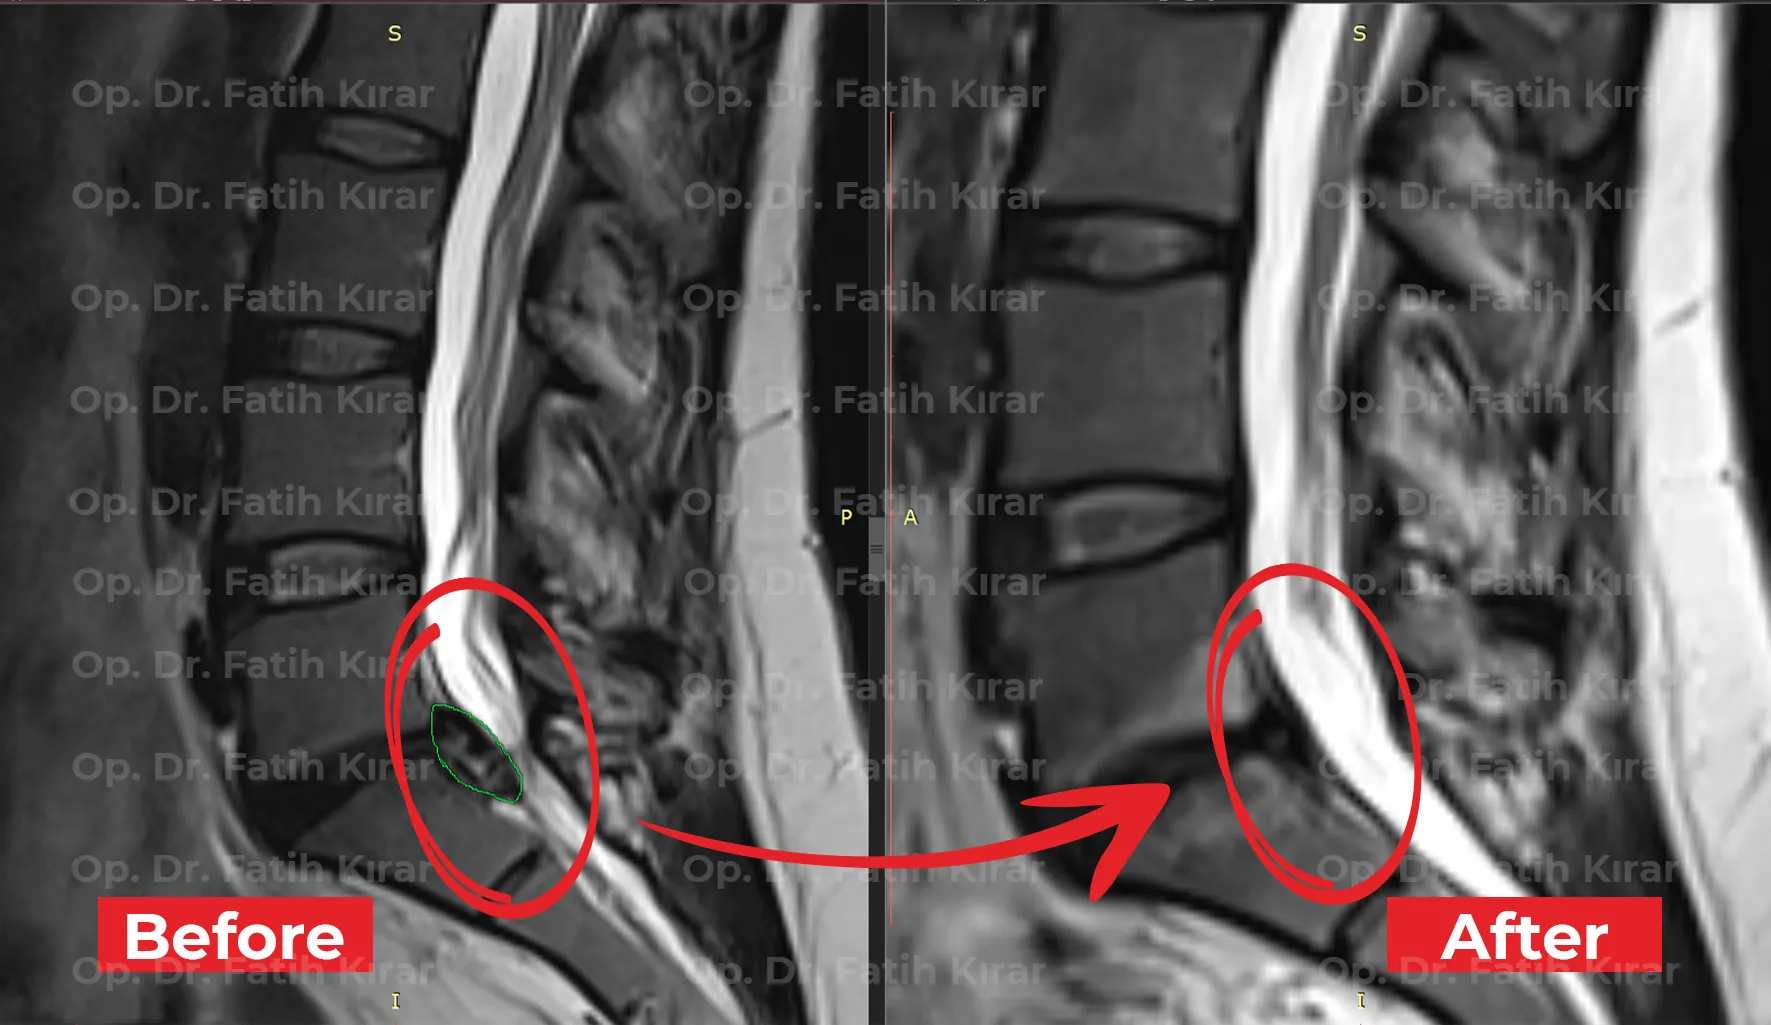

Advanced minimally invasive and non-surgical interventions with proven outcomes. MRI results demonstrating successful treatment of spinal conditions.

Neurosurgical treatment MRI - Clinical success